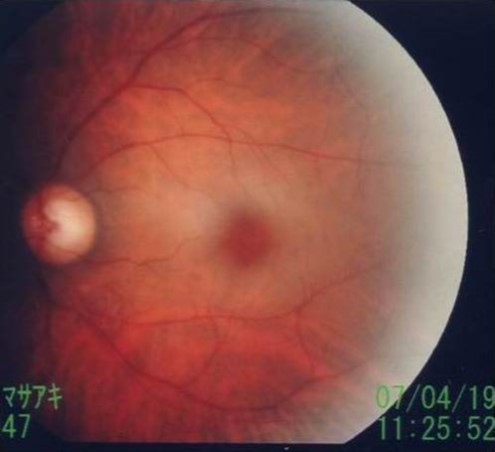

The following day (April 19, 2007), the corrected visual acuity of the left eye was 1.2; funduscopy showed a cherry red spot, characteristic of CRAO (Figure 4). Vision in the left eye subsequently improved gradually. At hospital discharge, although not perfect, vision had improved to the point where no impairment to daily activities was present.

Figure 4.Cherry red spot. Funduscopy showed a cherry red spot.

Cherry red spot. Funduscopy showed a cherry red spot.

During the acute phase, within a few hours after onset, the retina appears normal, with characteristic findings developing within 24 h. The posterior pole of the retina is edematous and opaque, the retina thins at the fovea, and red coloration of the choroid is visible as a “cherry red spot” on funduscopy (Figure 4)8.